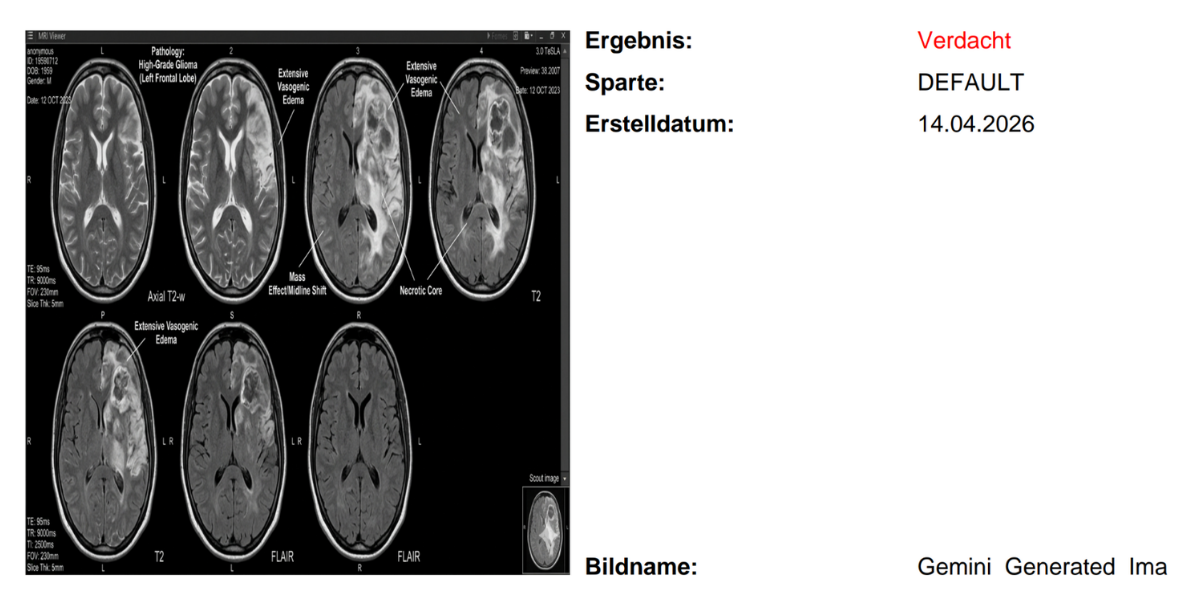

Lange galten medizinische Bilddaten als verlässliche „Quelle der Wahrheit“. Röntgenbilder, MRTs oder CT-Scans lieferten scheinbar eindeutige Beweise für Diagnosen und bildeten die Grundlage für Leistungsentscheidungen in der Versicherungswirtschaft. Doch dieser Status gerät zunehmend ins Wanken, denn manipulierte Röntgenbilder stellen eine neue Herausforderung für Versicherer dar.

KI Röntgenbilder können so überzeugend sein, dass selbst erfahrene Radiologen sie oft nicht sicher von echten Aufnahmen unterscheiden können. Den Umfang dieser neuen Problematik, zeigen neueste Berichte wie "Täuschend echt: KI fälscht Röntgenbilder - selbst Radiologen fallen darauf herein", der Frankfurter Rundschau und anderer Medien.

Manipulierte Röntgenbilder sind medizinische Aufnahmen, die mithilfe von Künstlicher Intelligenz oder Bildbearbeitung gezielt verändert oder vollständig neu erzeugt werden. Ziel ist es meist, Krankheiten vorzutäuschen oder zu verschleiern, um finanzielle Vorteile zu erlangen. Durch den rasanten Fortschritt der KI lassen sich heute Bilder erzeugen oder verändern, die von Originalaufnahmen kaum zu unterscheiden sind. Was als „Deepfake“ in sozialen Netzwerken begann, hat längst kritische Bereiche erreicht. Versicherungen stehen deshalb vor einer neuen Dimension des Abrechnungsbetrugs.

Hervorgebracht wurde die Relevanz durch eine im Fachjournal Radiology veröffentlichte Studie (Tordjman, Yuce et al.). Diese zeigt eindrücklich, wie realistisch KI-generierte Röntgenbilder inzwischen sind, weshalb auch das deutsche Ärzteblatt warnt:

• Täuschend echte Bilder: Moderne KI-Modelle erzeugen anatomisch plausible Aufnahmen, die kaum von echten zu unterscheiden sind.

• Unsicherheit bei Fachärzten: In einer Untersuchung mit 17 Radiologen aus sechs Ländern wurden nur 41 % der KI-Bilder spontan als Fälschung erkannt – sofern nicht vorab darauf hingewiesen wurde.

• Erfahrung schützt nicht: Die Berufserfahrung hatte keinen signifikanten Einfluss auf die Erkennungsrate.

• Niedrige Einstiegshürden: Täuschend echte Bilder lassen sich heute per einfacher Texteingabe generieren – ohne Spezialkenntnisse.